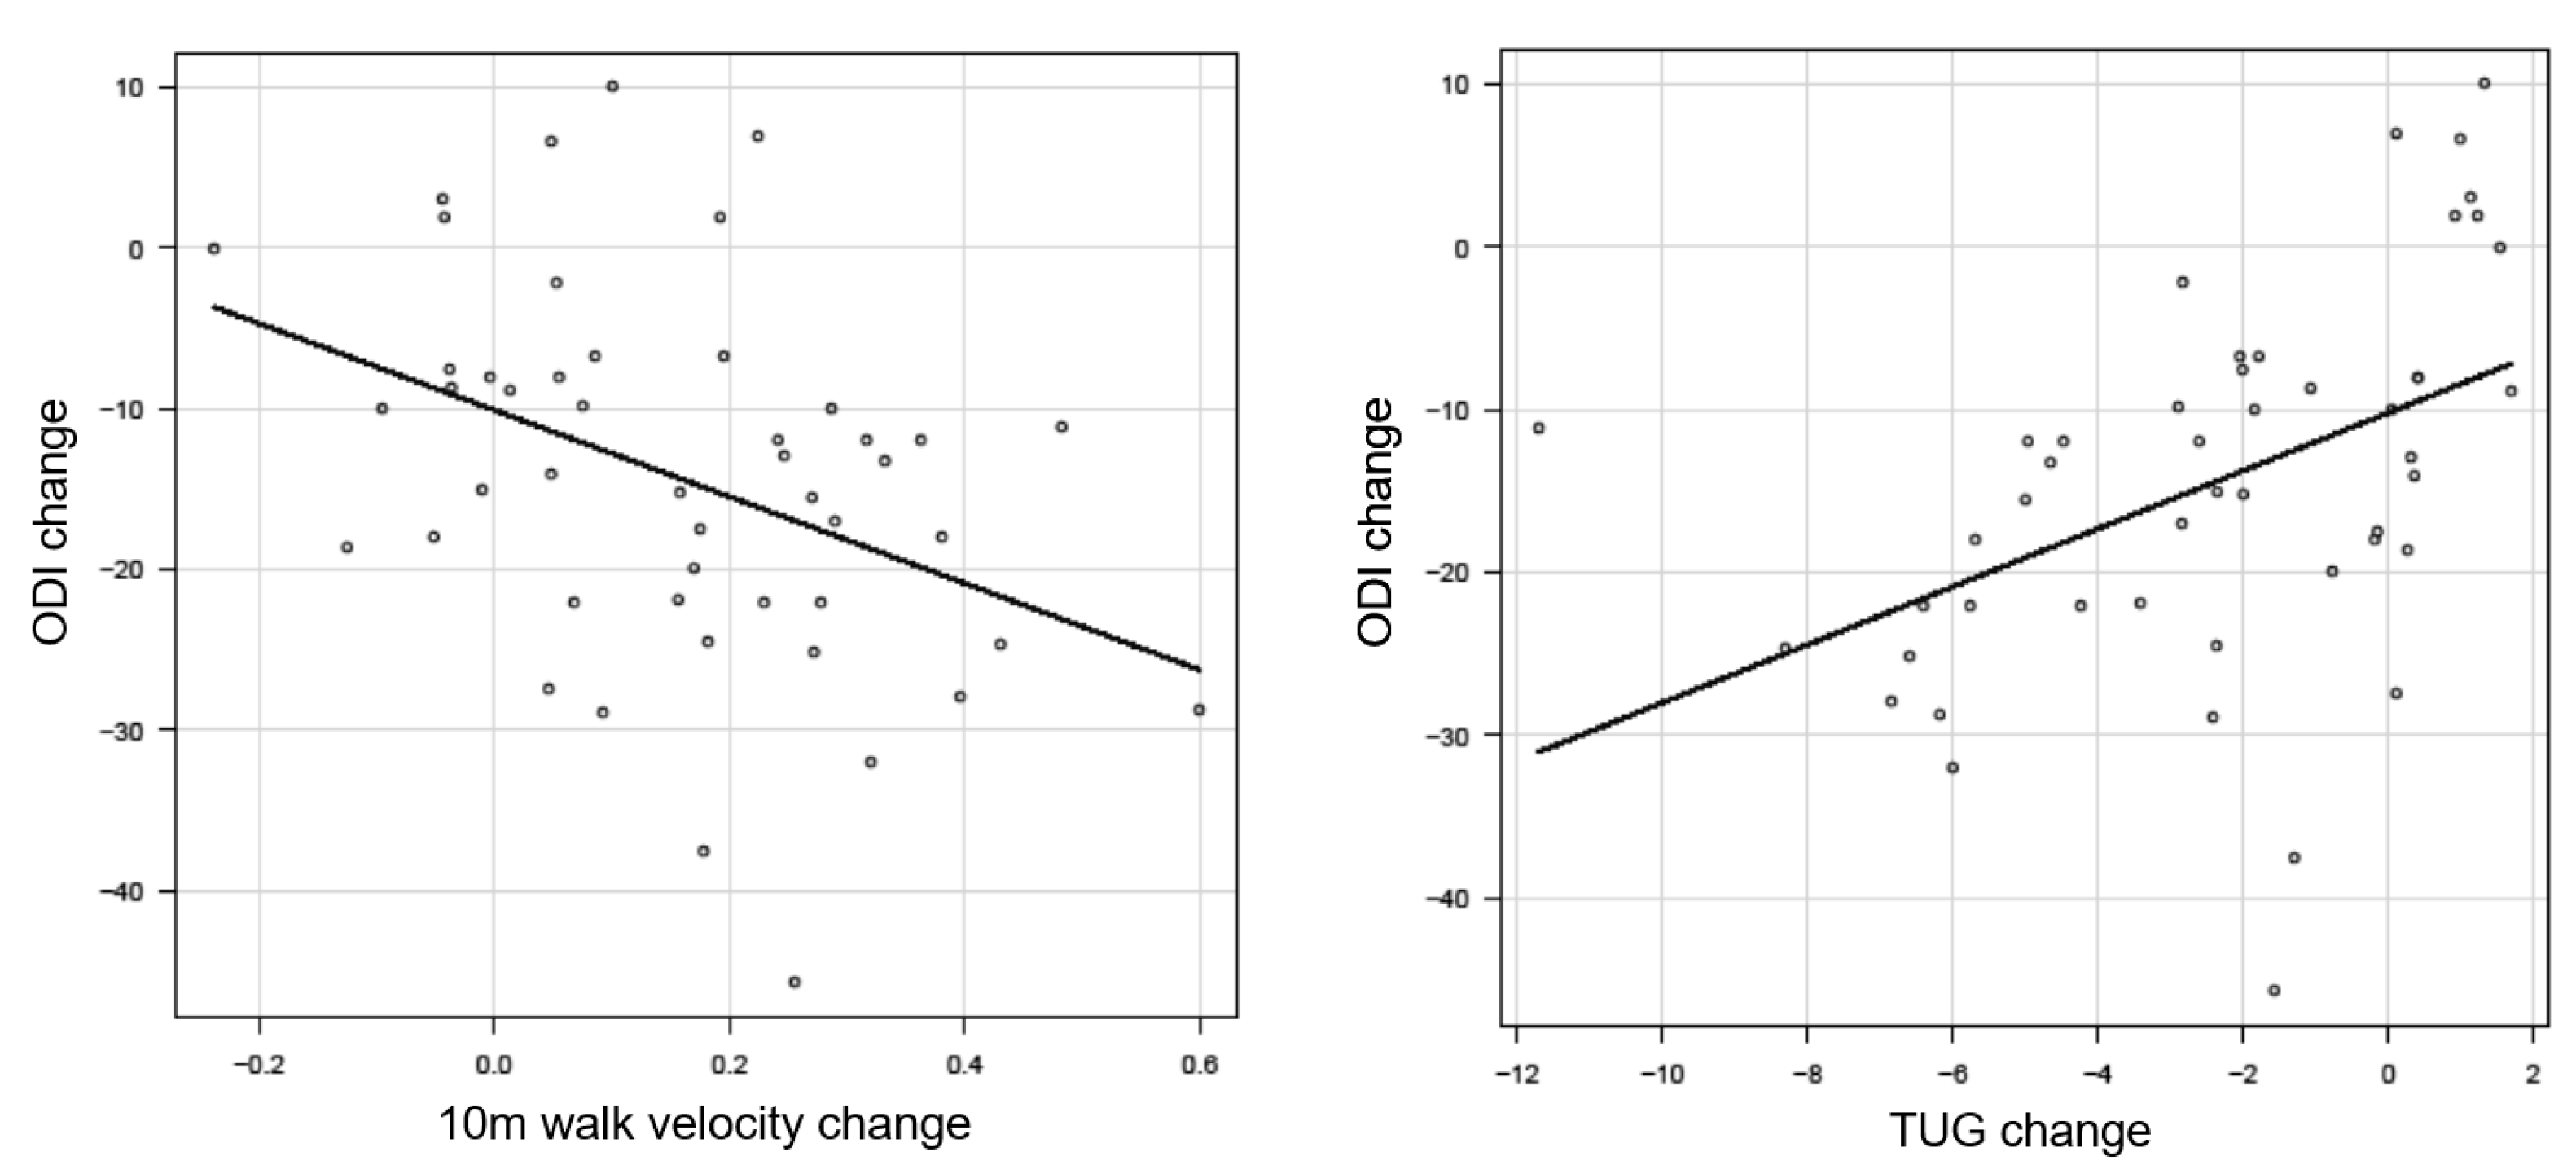

3.3. External Responsiveness

3.3.1. Anchor-Based Approach

| 10 m Walk Velocity | Change ODI (n = 30) |

|---|---|

| Anchor-Based Approach | |

| Average change 10 m walk velocity | 0.22 ± 0.2 |

| Change difference 10 m walk velocity | 0.18 |

| ROC analysis | |

| AUC (95% CI) | 0.8 |

| Cutoff value | 0.10 |

| Sensitivity | 0.78 |

| Specificity | 0.77 |

| Timed Up and Go Test | Change ODI (n = 30) |

|---|---|

| Anchor-Based Approach | |

| Average change 10 m walk velocity | −3.6 ± 2.9 |

| Change difference 10 m walk velocity | −3.3 |

| ROC analysis | |

| AUC (95% CI) | 0.85 |

| Cutoff value | −2.04 |

| Sensitivity | 0.89 |

| Specificity | 0.67 |